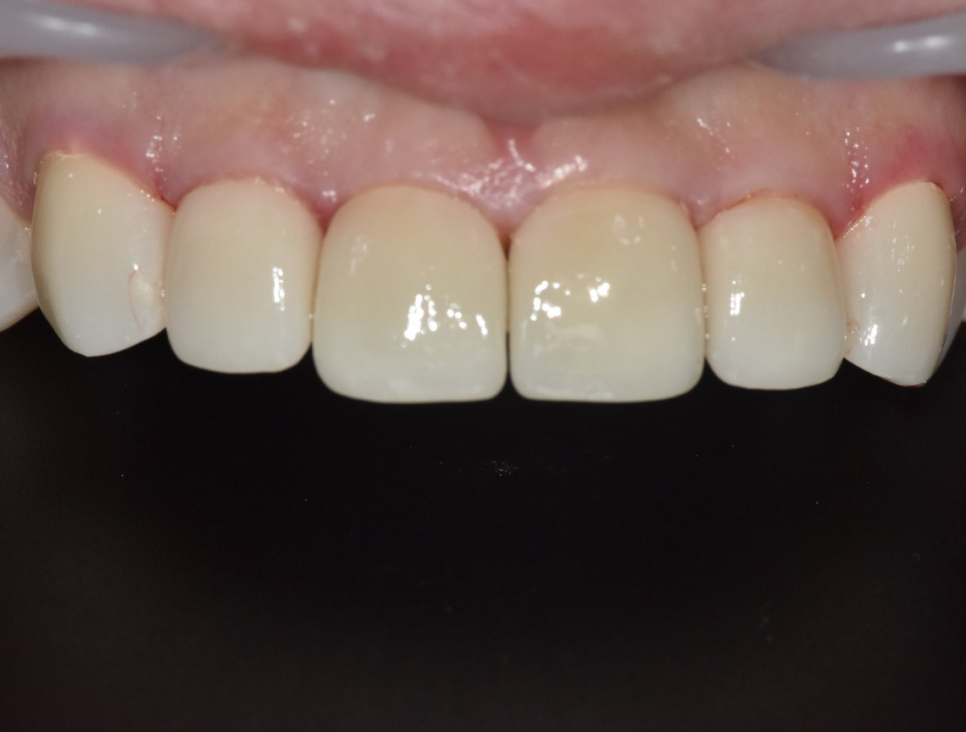

치료가 끝난 모습입니다.

치료 전과 비교해 보았을 때 하얀 반점도 사라지고고, 치아도 가지런해졌습니다.

앞니를 살짝 길게 디자인해서 아래 앞니 반점도

자연스럽게 가려지는 상태입니다.